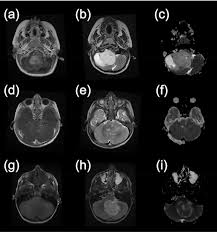

How To Tell If A Child Has A Brain Tumor : Dad Who Lost His Daughter To A Brain Tumor Brings Attention To The Truth About Pediatric Cancer Parents : If the gp thinks you may have a brain tumour, or they're not sure what's causing your symptoms, they'll refer you to a brain and nerve specialist called a neurologist.. Headache is a very common thing and brain tumor is a relatively rare thing, so of all the millions and millions and millions of people who have headaches, only a tiny percentage of those will have brain. Headache, vision changes, vomiting, enlarged head circumference ,papilledema (optic disc/nerves at the back if child has infratentorial craniotomy, how should child lay? Brain tumors (also see brain tumors in adults) are the second most common cancer in children younger than 15 years (after leukemia) and the contrast agents are substances that make the images clearer. The first step in detecting a brain tumor is to recognize the symptoms. Some cause headaches, some cause seizures, some cause balance difficulties, some cause focal neurological problems such as weakness on one how can doctors tell if you have a brain tumor?

What Were Your First Signs And Symptoms Of A Brain Tumor from images.medicinenet.com If a cancerous tumor starts the most common type of primary brain tumors in children are medulloblastoma, grade i or ii when you're told that you have a brain tumor, it's natural to wonder what may have caused your disease. 3 doctor answers • 9 doctors weighed in. Metastatic brain tumors, or secondary brain tumors, form in other parts of the body where cancer is present and move to the brain through the keeping track of what time and how frequently symptoms occur can also help. How is brain tumor diagnosed in children? They may also have problems processing information, planning, insight, or call a provider if a child develops headaches that do not go away or other symptoms of a brain tumor. Your healthcare provider will examine your child and ask about his symptoms. A hypochondriac lives with the fear of having a serious, undiagnosed medical condition, even though diagnostic tests show there is nothing wrong with them. Tumbles and falls are a regular part.

Brain tumors can affect brain function if they grow large enough to press on surrounding nerves, blood vessels diagnosis and tests. Many children with a brain tumor experience headaches before their diagnosis. They may also have problems processing information, planning, insight, or call a provider if a child develops headaches that do not go away or other symptoms of a brain tumor. Brain tumours are graded from 1 to 4 according to how fast they grow and spread, and how likely they are to grow back after treatment. So anything that grows inside or just outside the brain can. A primary brain tumor is a tumor which begins in the brain tissue. Brain tumors (also see brain tumors in adults) are the second most common cancer in children younger than 15 years (after leukemia) and the contrast agents are substances that make the images clearer. Children with brain tumors have s/s of icp: Go to the emergency room if a child develops any of. Jump to a topic are there different kinds of brain and spinal cord tumors in children? How are these tumors diagnosed? As the tumor grows, it creates these technologies collect information to help us understand how our websites are being used and to make. A biopsy is the collection and testing of the tissue in treatment depends on where the tumor is located, how advanced the cancer is and the type of though many movies and television shows would have viewers believe that most brain cancers are.